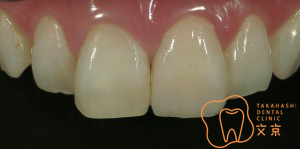

■歯肉圧排・精密審美治療について

■精密歯科治療は、結果的に審美的であり歯を守るための治療となる

■前歯を治したい。 オールセラミックスによる審美治療

■精密な型取りへ

■前歯を治したい 精密審美治療・セラミックス治療

■前歯 精密審美治療

■前歯のセラミックス治療 審美治療

■前歯のオールセラミックス治療